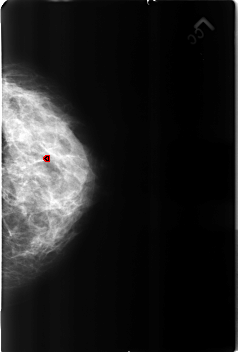

B_3162_1.RIGHT_CC

FILE: B_3162_1.LEFT_CC.OVERLAY

TOTAL_ABNORMALITIES 1

ABNORMALITY 1

LESION_TYPE CALCIFICATION TYPE LUCENT_CENTER DISTRIBUTION N/A

ASSESSMENT 2

SUBTLETY 4

PATHOLOGY BENIGN_WITHOUT_CALLBACK

TOTAL_OUTLINES 1

BOUNDARY